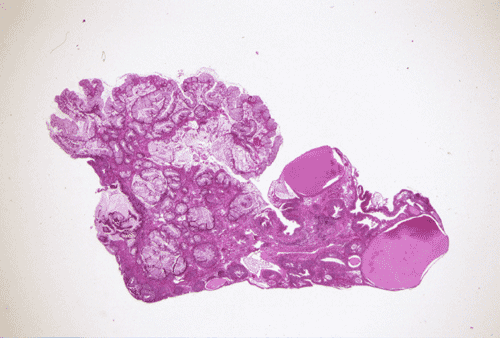

A questionable mass and several areas of bullous edema near the dome of the urinary bladder were found by cystoscopy. The suspicious areas were biopsied and yielded the material being shown here.

The biopsy material showed polypoid fragments with cystically dilated glands lined by columnar to cuboidal cells (Panel A, B, and C). Some of the glands were lined by transitional epithelium (Panel D), some were lined by a mixed transitional epithelium and mucin producing columnar epithelium (Panel E), and some were lined entirely by mucin producing columnar epitheliuim (Panel F) that closely resembled colonic epithelium. A mild to moderate degree of chronic inflammatory cell infiltration was also present. A mixed population of mucin producing columnar epithelium with transitional epithelium was also noted in many of the non-glandular surface epithelium (Panel G). No dysplasia was found.

DIAGNOSIS: Polypoid cystitis cystica et glandularis, intestinal type.